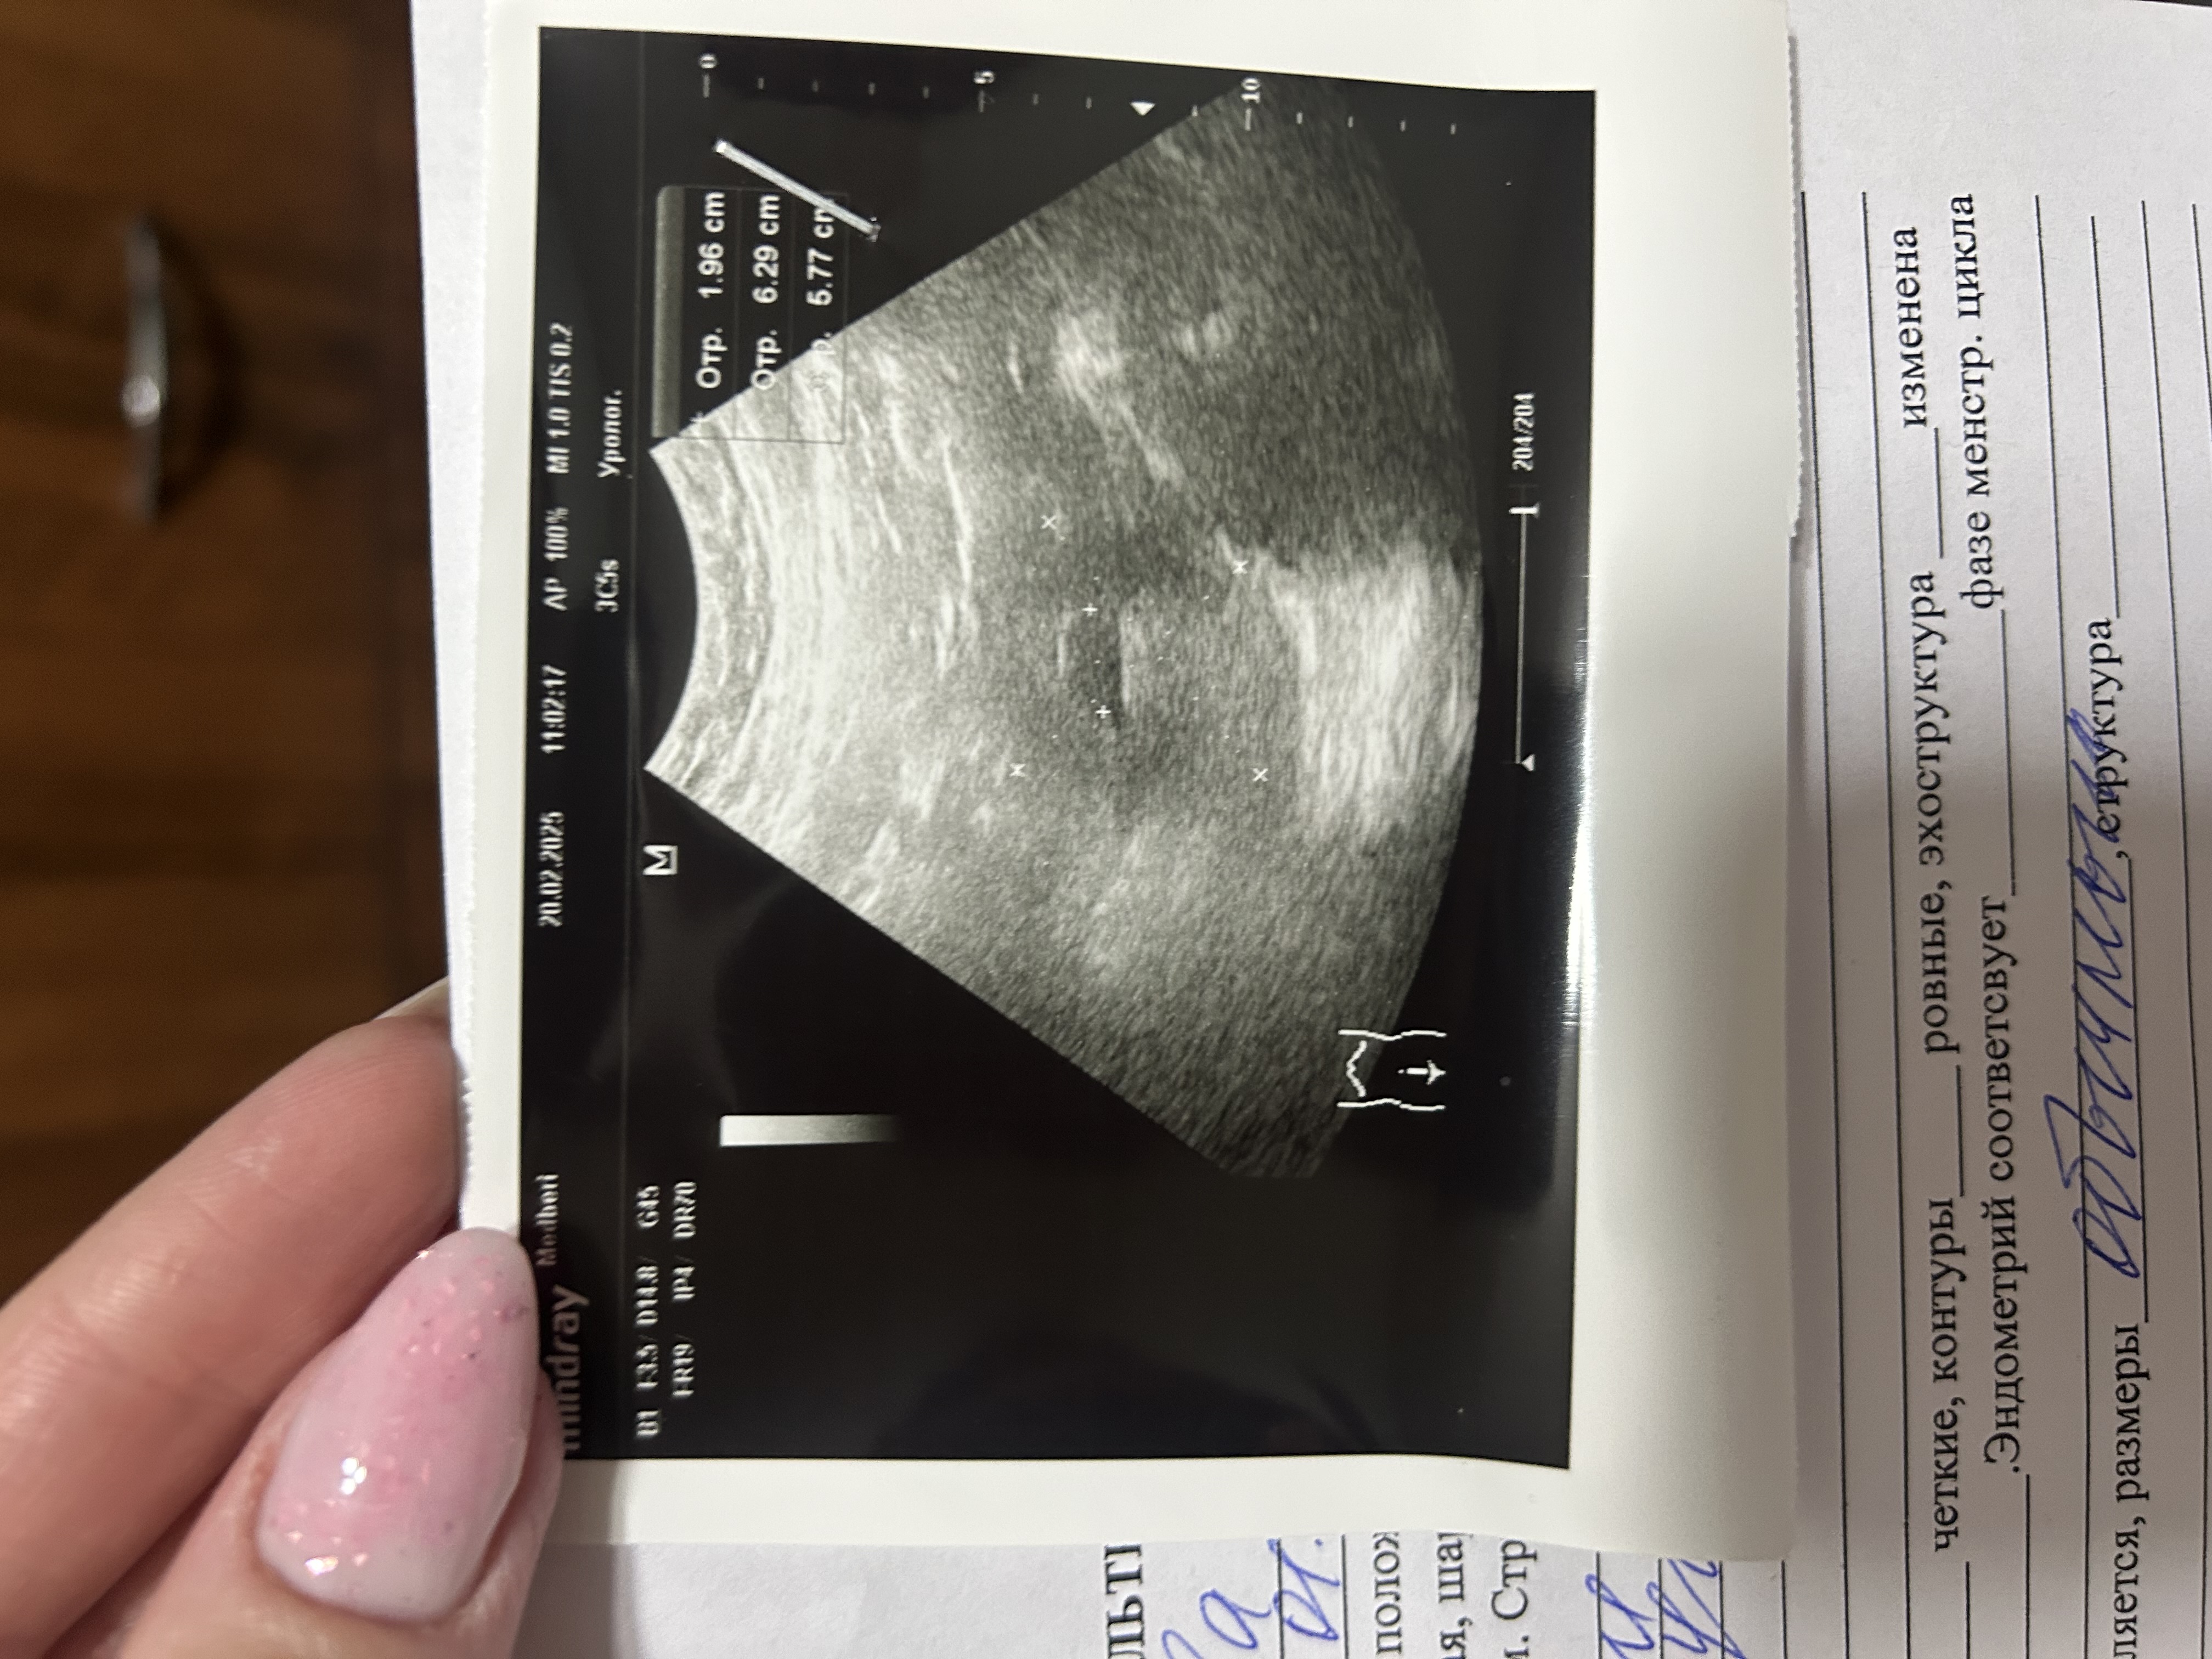

Какое то большое ПЯ для срока 5 недель

Вишня, ну вот и я такого же мнения . Может аппарат ошибся или я даже не знаю , что еще может быть . Кучу всего передумала уже

Марии , это узи я делала 20 февраля . Вот только симптомы беременности нарастают. Грудь болит ,тошнит ,изжога ,голова болит ,кажется уже живот немного прибавился снизу . Не понимаю и надеюсь 🙏